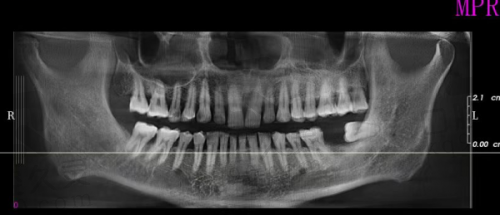

当我第一次走进娄底协合口腔医院时,就被其温馨舒适的环境所吸引。医院的装修风格简洁大方,候诊区宽敞明亮,摆放着舒适的沙发和绿植,给人一种放松的感觉。医护人员的服务态度也非常热情周到,一进门就有导医主动上前询问我的需求,并引导我完成挂号等一系列流程。在与医生沟通的过程中,我感受到了医生的专精和耐心。医生详细地询问了我的牙齿情况、病史以及生活习惯等信息,然后为我进行了全方面的口腔检查。通过口腔CT等精良设备,医生清晰地了解了我牙齿缺失部位的骨量、牙槽骨情况等,为后续的种植牙方案制定提供了正确的依据。这让我对娄底协合口腔医院种植牙的专精性有了初步的信任。